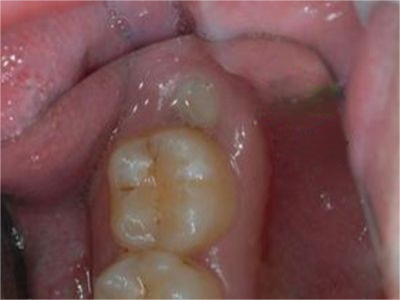

阻生牙是指由于邻牙、骨或软组织的阻碍而只能部分萌出或完全不能萌出,且以后也不能萌出的牙。引起牙阻生的成因,主要是由于颌骨缺乏足够的空间容纳全部恒牙。常见的阻生牙为下颌第三磨牙、上颌第三磨牙及上颌尖牙。

阻生牙可反复引起冠周炎,或引起邻牙牙根吸收和破坏,位置不正,不能完全萌出,好发部位是上、下颌第三磨牙。